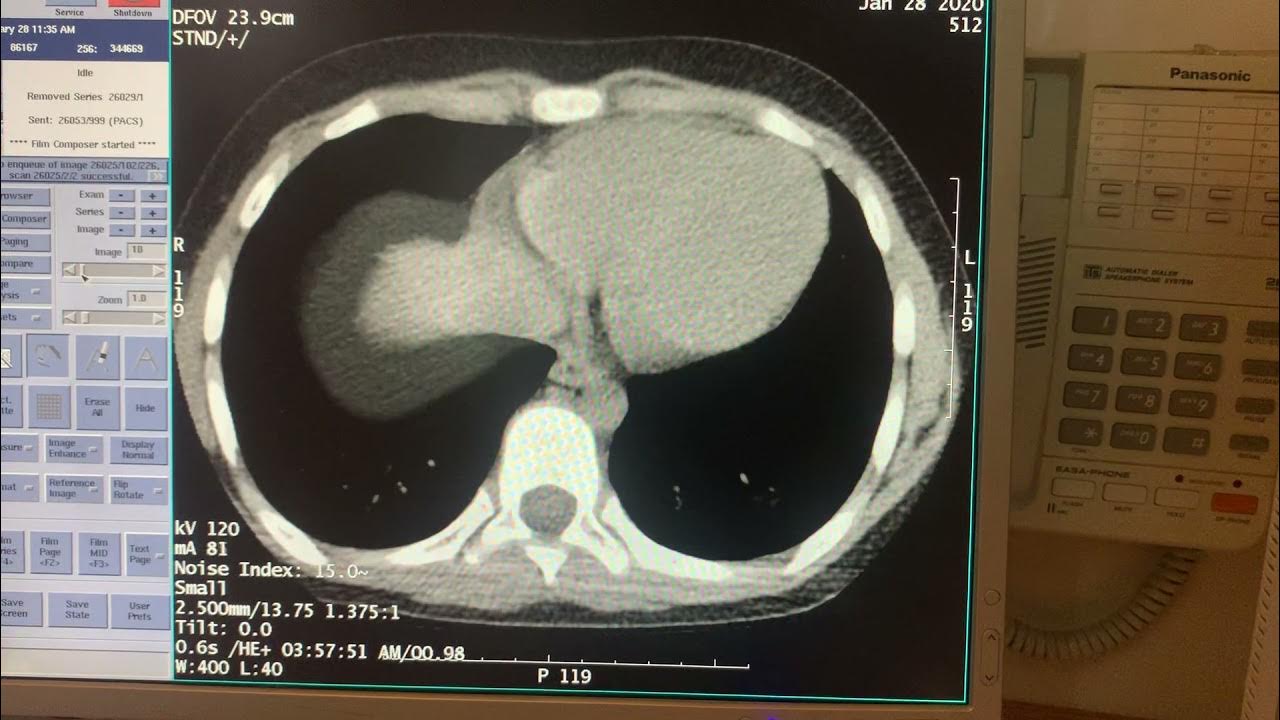

Example of CT Scan Streak Artifact YouTube Streak Artifact From Dental Hardware Dental hardware produces streak artifacts on computed tomography (ct) images reconstructed. the aim of this study was to evaluate different metal artifact reduction techniques for metal artifacts induced by. in ct imaging, streak artifacts are a common problem. background dental hardware produces streak artifacts on computed tomography (ct) images reconstructed with the standard weighted. learn about. Streak Artifact From Dental Hardware.

CT Streak Artifact Example YouTube Streak Artifact From Dental Hardware the aim of this study was to evaluate different metal artifact reduction techniques for metal artifacts induced by. background dental hardware produces streak artifacts on computed tomography (ct) images reconstructed with the standard weighted. in ct imaging, streak artifacts are a common problem. Dental hardware produces streak artifacts on computed tomography (ct) images reconstructed. learn about. Streak Artifact From Dental Hardware.